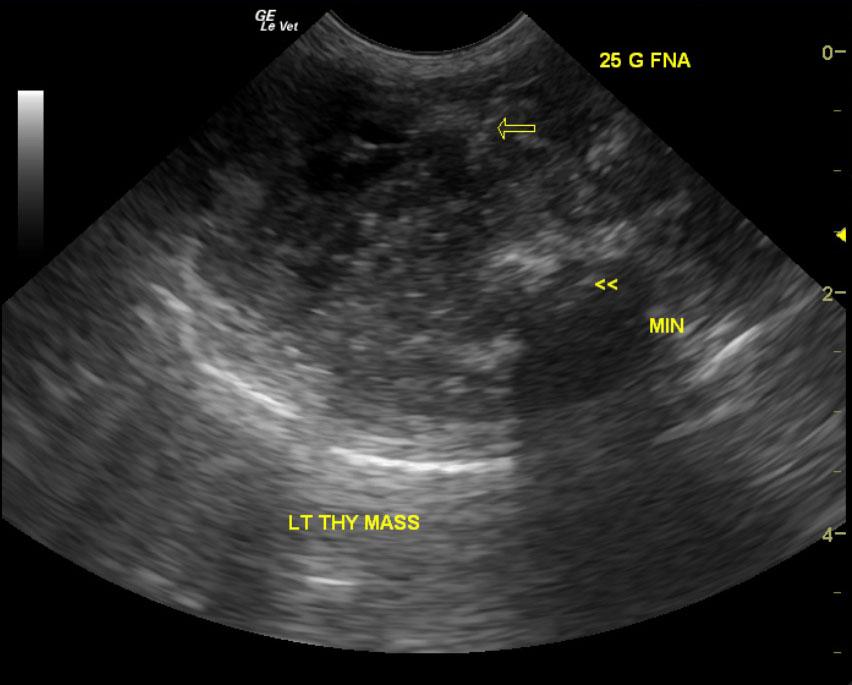

A 9-year-old male neutered Plotthound dog was presented for evaluation of polyuria, polydypsia, and occasional loose stool. Abnormalities on CBC and serum biochemistry included mild anemia, mild leukopenia, mildly increased ionized calcium, and mild azotemia. T4 was within reference range at 4.4.